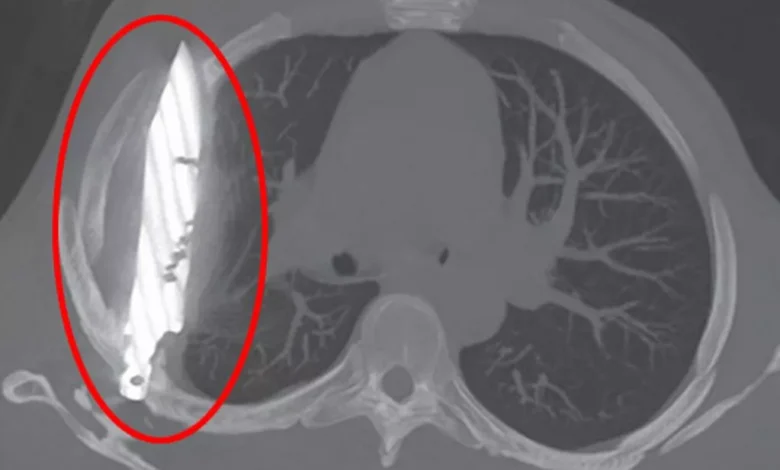

Une radiographie thoracique a été réalisée après sa plainte et elle a révélé la cause de son mal actuel : une grande lame de couteau logée au milieu du thorax.

Les médecins ont constaté que le couteau avait pénétré l’omoplate droite et avait réussi à éviter les organes vitaux.